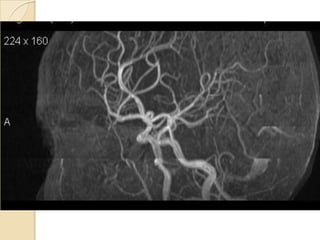

NORMAL MRA

Arteries of the brain (cranial view) - MRA

1. Anterior cerebral artery

2. Anterior communicating artery

3. Basilar artery

4. branches (in insula) of middle

cerebral artery

5. Cavernous portion of internal

carotid artery

6. Cervical portion of internal carotid

artery

7. Genu of middle cerebral artery

8. Intracranial (supraclinoid) internal

9. Middle cerebral artery

10. Ophthalmic artery

11. Petrous portion of internal carotid

12. Posterior cerebral artery

13. Posterior cerebral artery in ambient

cistern

14. posterior cerebral artery in

interpeduncular cistern

15. Posterior communicating artery

16. Posterior inf cerebellar artery.

17. Quadrigeminal portion of posterior

18. Superior cerebellar artery

19. Vertebral artery